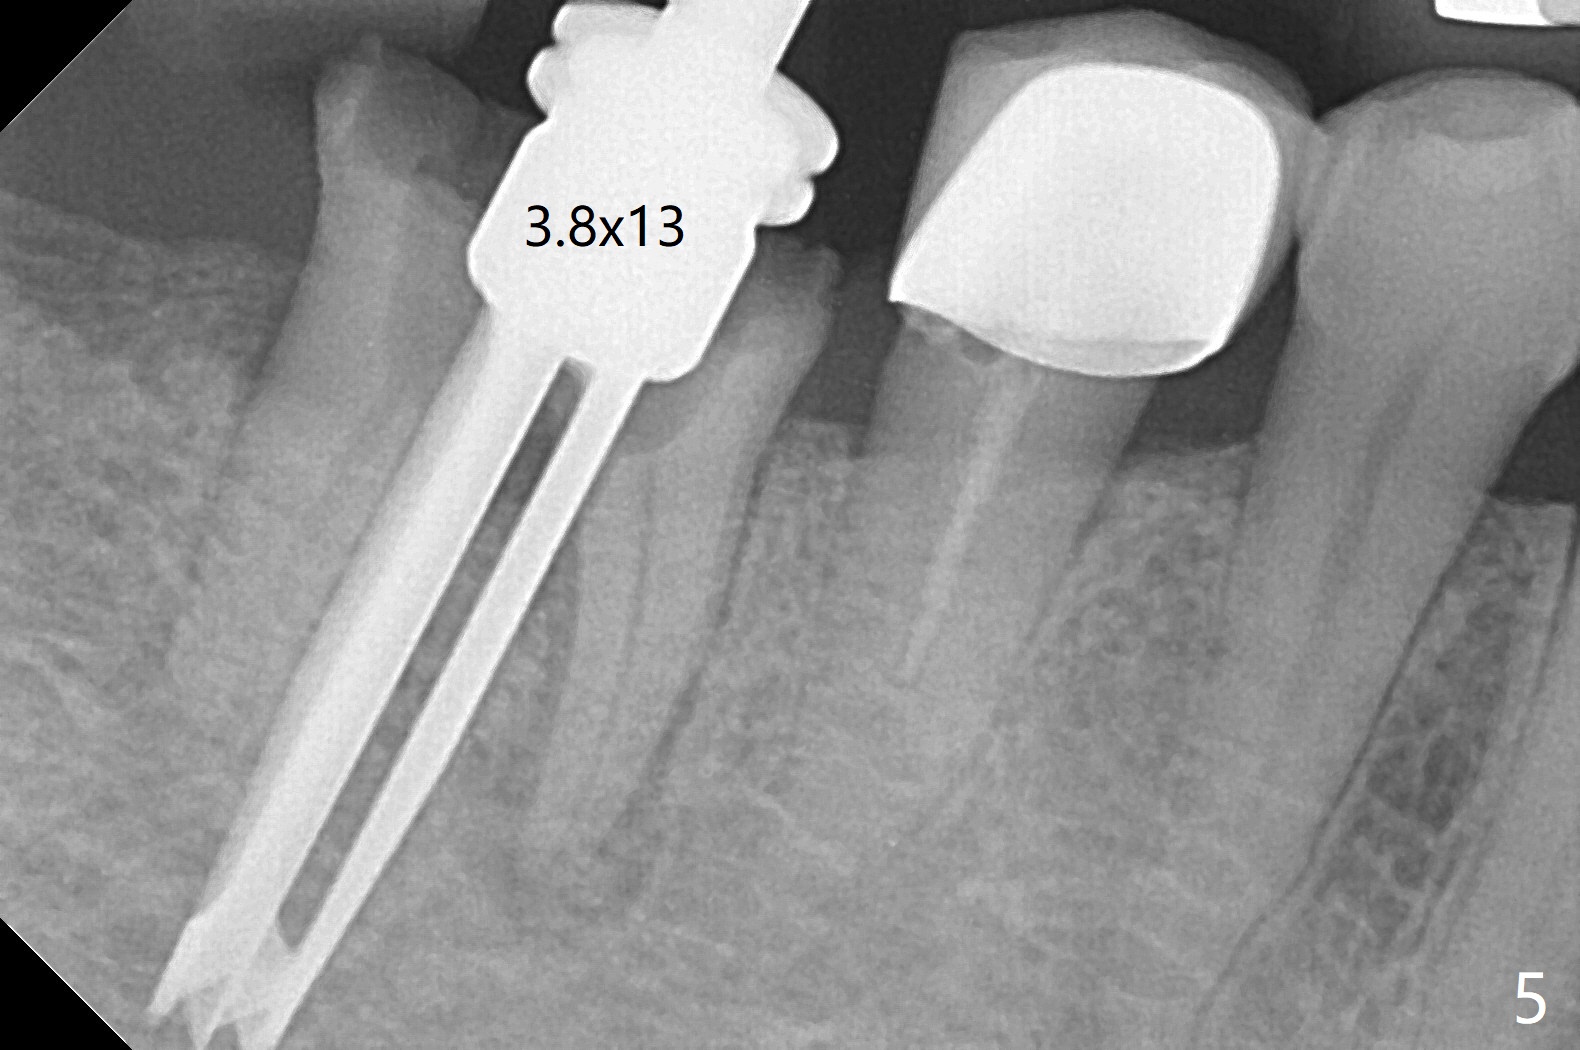

A 59-year-old woman with severe pain and mobility at #30 returns to clinic for extraction and implant on emergency basis (Fig.1 ^: crazing line). To prevent osteotomy deviation off the septum, the crown is sectioned (Fig.2) and the coronal end of the septum is exposed. In fact the initial osteotomy is blind (Fig.3). After increasing the access (Fig.4), trying to change trajectory and increasing the depth and diameter of the osteotomy, the trajectory deviates to the distal socket (Fig.5). Following root extraction, debridement of the sockets and minor trajectory change, a 4x11 mm dummy implant is placed (Fig.6). With a drastic change in osteotomy, the dummy implant position is somewhat acceptable with a 5.2x4 mm planning abutment (Fig.7 P). After placement of bone graft around the 4.5x11 mm final implant to enhance stability, a 5.5x4(3) mm definitive abutment is placed in a restorable position (Fig.8). The implant turns while the abutment screw is hand tightened. Since there is an apical space (Fig.8 <), the implant is then placed ~ 1mm deeper with ~ 30 Ncm (Fig.9). A longer cuffed abutment is inserted and more bone graft is placed (*). In summary, roots in the sockets do not seem to help free hand osteotomy in the lower 1st molar. It is also difficult to control pain during acute infection. Block anesthesia has to be administered, increasing the chance of nerve injury. Either guided surgery or delayed implant should be conducted. There is no postop paresthesia, although the buccal gingiva is slightly erythematou, edematous and tender 1 week posotp. Oral Amoxicillin is prescribed for one more week. The keratinized gingiva (Fig.10 ^) and the papilla (*) are maintained in place around the immediate provisional (P) 2 months 20 days postop. The soft tissue remains normal 4 months postop (Fig.11) and immediate pre cementation (Fig.12).